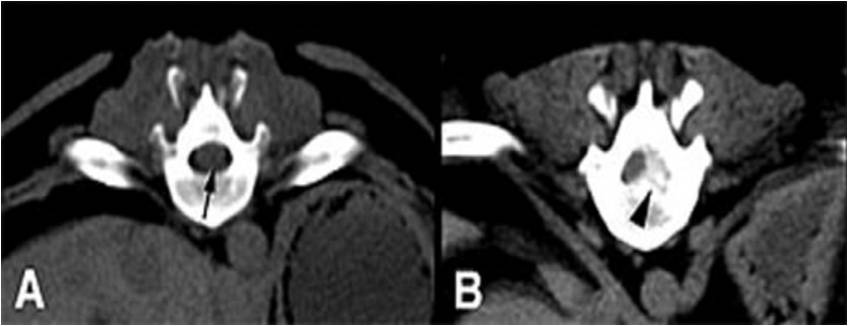

Η απλή ακτινογραφία δείχνουν κάποια ευρήματα όπως η στένωση των μεσοσπονδυλίων διαστημάτων, η δημιουργία οστεόφυτων και η απώλεια της λόρδωσης, όμως δεν στοιχειοθετεί διάγνωση της σπονδυλικής στένωσης και περισσότερο χρησιμοποιείται για να αποκλείσει άλλες παθολογίες. Η διάγνωση της σπονδυλικής στένωσης γίνεται από την μαγνητική τομογραφία (MRI) , που δείχνει με ακρίβεια το εύρος του σπονδυλικού σωλήνα και των τρημάτων, την ύπαρξη προβολής ή κήλης μεσοσπονδυλίου δίσκου, την πίεση στις νευρικές ρίζες και την υπερτροφία του ωχρού συνδέσμου. Ο συνδυασμός αξονικής τομογραφίας με μυελογραφία (CT μυελογραφία) μπορεί να χρησιμοποιηθεί σε περιπτώσεις που αντενδείκνυται η MRI, όπως σε χρήση βηματοδότη ή υλικών οστεοσύνθεσης, όμως παρά την απεικονιστική της αξία έχει ως μειονέκτημα το γεγονός πως είναι επεμβατική μέθοδος και συχνά έχει επιπλοκές όπως πονοκέφαλο, εμετούς, μηνιγγίτιδα κ.α.

Για να οριστεί διάγνωση σπονδυλικής στένωσης πρέπει η εγκάρσια επιφάνεια του να είναι λιγότερο από 100 mm2. Βέβαια, η απεικονιστική στένωση του σπονδυλικού καναλιού δεν συνεπάγεται συσχέτιση του απεικονιστικού ευρήματος με την ύπαρξη πόνου από αυτό σαν αιτία. Έρευνες έχουν δείξει πως σε άτομα άνω των 60 ετών τα ποσοστά ασυμπτωματικών ατόμων με στένωση του σπονδυλικού σωλήνα φτάνουν το 30%. Αυτό πρακτικά σημαίνει πως η ύπαρξη ενός στενωτικού καναλιού δεν χρήζει πάντα θεραπείας, καθώς η αιτία του πόνου μπορεί να είναι διαφορετική. Για αυτό τον λόγο πάντα στην διάγνωση συνεκτιμώνται το ιστορικό του ασθενούς με την κλινική και απεικονιστική του εικόνα.